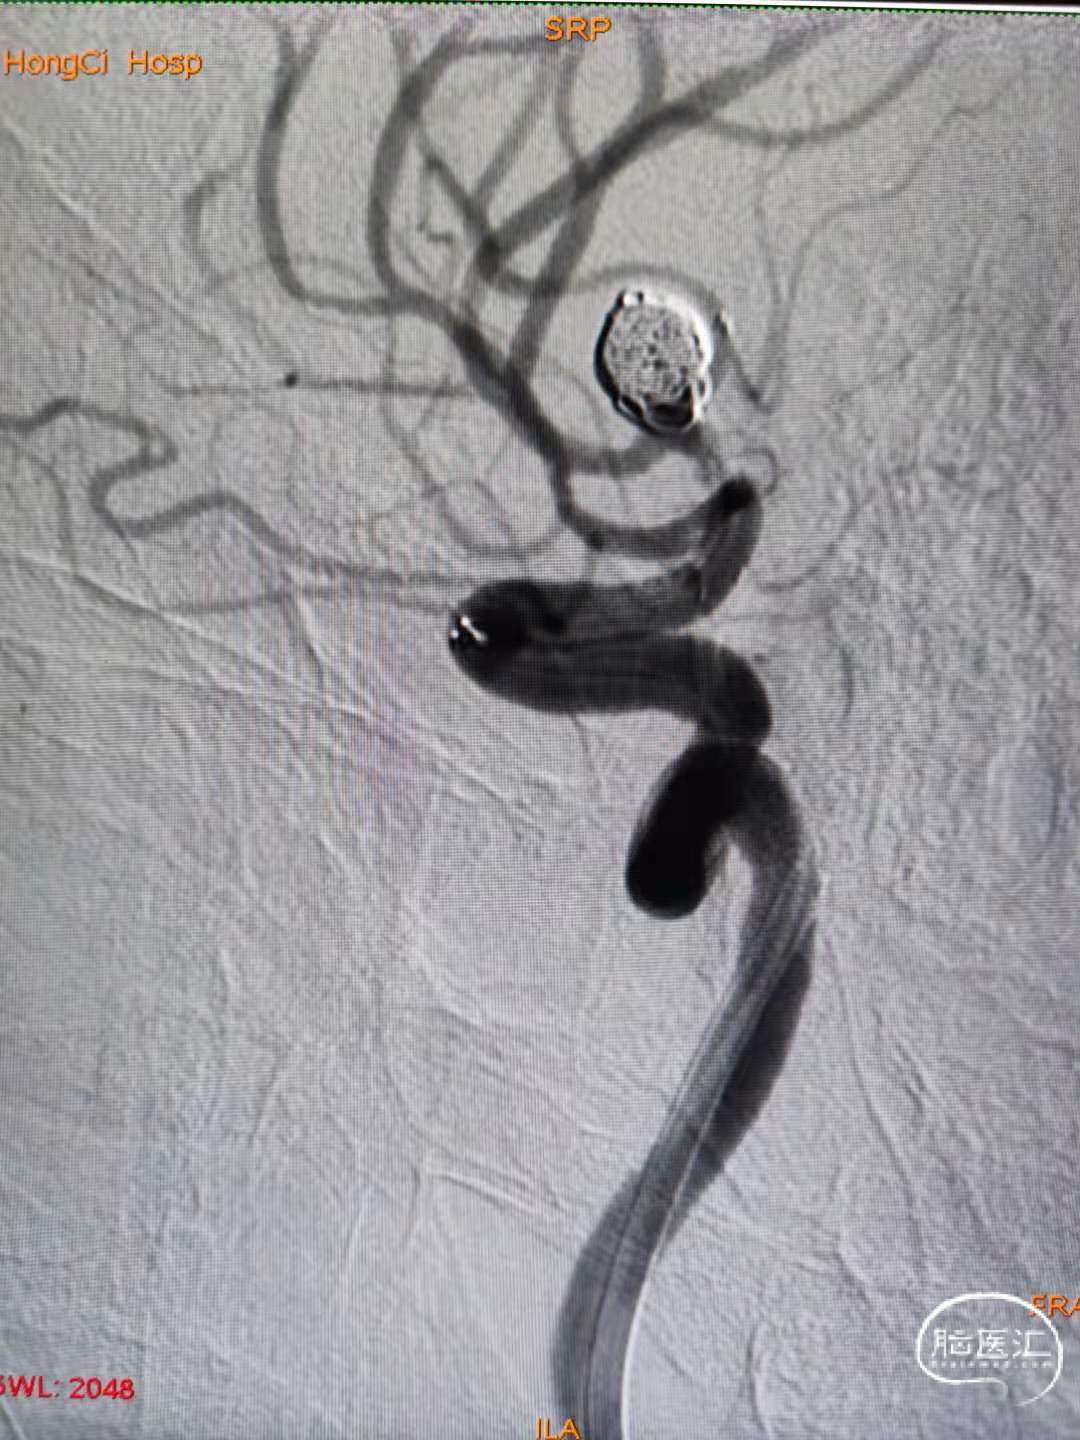

使用SL-10微导管和7*30弹簧圈。成篮满意后释放Atlas 3.0*15支架。支架释放并打开顺利,随后将支架导管穿网眼送入动脉瘤腔内。

3、随后经送入动脉瘤腔内的微导管连续推送6*20、5*20,4*12、3*8、2*6、2*4弹簧圈。后造影显示动脉瘤栓塞满意,上下支干通畅,显影良好。

1、Atlas支架在小直径血管的表现良好,在本例动脉瘤的到位以及在仅1.0mm的上支干血管内打开顺利,为后续的栓塞治疗提供可靠的保证。

2、作为开环小径支架,Atlas轻松穿网孔性能,为单微管技术的使用提供可靠保障。